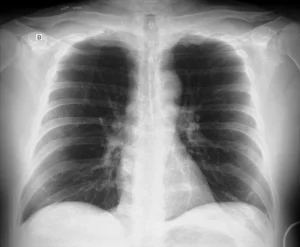

Radiografía de tórax en proyección anteroposterior (AP), obtenida en la cama del paciente, en decúbito supino, con inspiración subóptima. La segunda radiografia se obtuvo en proyeccion PA con el paciente de pie, observandose la silueta cardiaca de tamaño normal.

C – Corazón y mediastino

La silueta cardíaca se observa aumentada de tamaño, con contornos conservados. La relación cardiotorácica se encuentra aumentada.

Este hallazgo debe interpretarse en el contexto de una proyección anteroposterior, que produce una magnificación aparente del corazón debido a la mayor distancia entre la estructura y el detector.

Este caso ilustra el aparente aumento del tamaño de la silueta cardíaca observada en la radiografía de tórax obtenida en decúbito supino, en una proyección qué necesariamente es anteroposterior (AP).

En la proyección AP, especialmente en pacientes encamados, la silueta cardíaca se encuentra más alejada del detector, lo que produce una magnificación aparente del tamaño del corazón. Este efecto geométrico puede simular cardiomegalia en ausencia de un aumento real del tamaño cardíaco.

Por este motivo, la valoración del tamaño de la silueta cardíaca debe realizarse preferentemente en una radiografía PA obtenida en bipedestación. En la proyección AP, el hallazgo de un corazón aparentemente aumentado debe interpretarse con cautela y siempre en correlación con la técnica del estudio y la clínica del paciente.